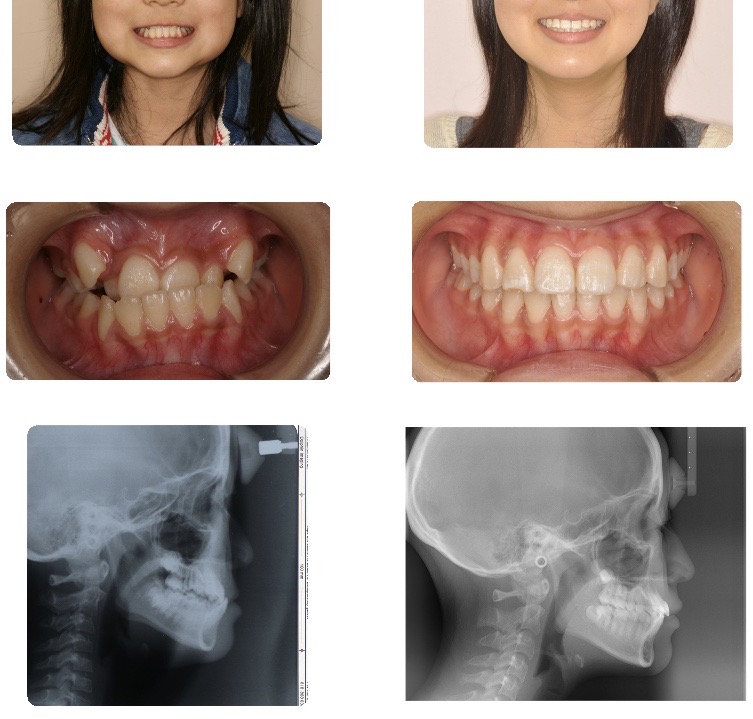

上顎前突(出っ歯)

リラックスした状態で口唇閉鎖が可能となり、オトガイの緊張が緩和されました。

側貌では上下口唇ともに後退し、自然な口元に改善されました。

また上顎前歯の後退により、前歯でものが咬みきれるようになりました。